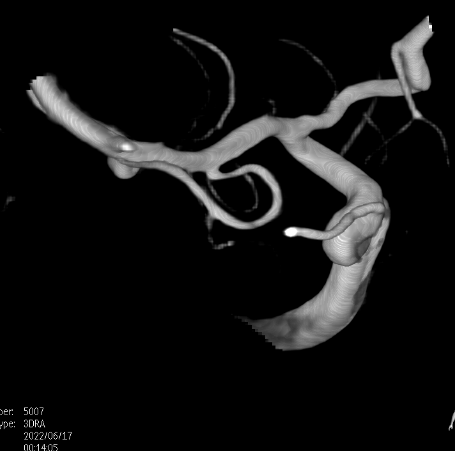

畅医达(Accessway)0.017支架微导管在0.014微导丝引导下顺利到达右侧大脑中动脉M2远端,经支架微导管引入畅医达(Choydar)血流导向装置,3mm*15mm,推送平顺,然后跨瘤颈缓慢释放支架,支架头端打开良好。

支架部分释放后复查造影示支架位置良好,缓慢完全释放支架,支架打开良好,复查造影示支架位置良好,完全覆盖瘤颈,贴壁佳,瘤囊内可见造影剂滞留明显,OKM分级A3。

Vaso CT显示 畅医达(Choydar)血流导向装置 位置良好,完全覆盖瘤颈,长轴及横轴薄层均显示支架贴壁良好。